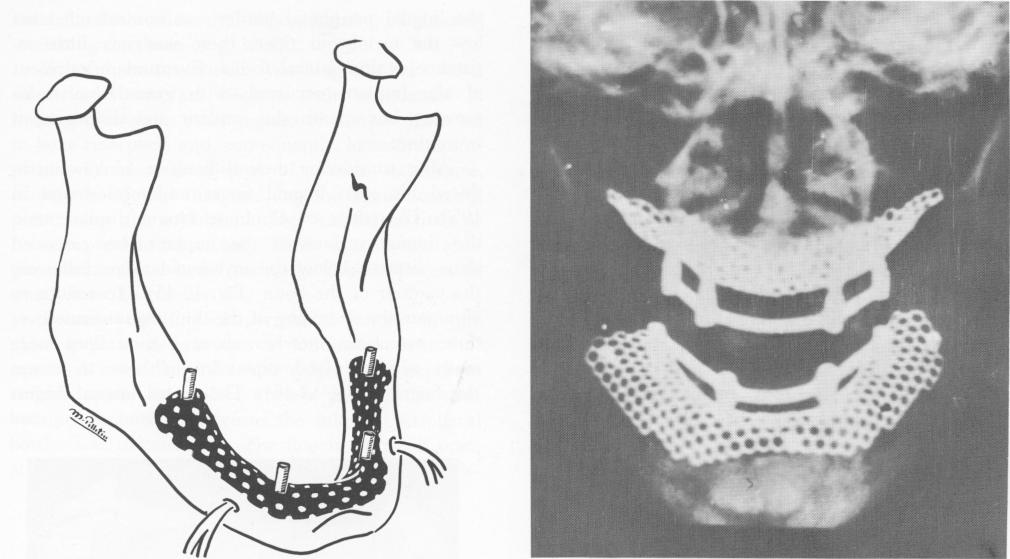

Fig. 12-42. The Marziani-designed tantalum subperiosteal implant.

Finally, the implant is positioned over the ex-posed mandibular bone (Fig. 12-42). For immediate fixation, a few screws are passed through the implant and into the bone in the areas of the external oblique ridges and symphysis.

The tissues are sutured over the implant and the prefabricated lower denture is hollowed out and fitted to the four abutments with the use of fast-setting acrylic. The case is occluded and balanced out. Roentgenograms are taken periodically to analyze the situation (Fig. 12-43) .

Fig. 12-43. A posteroanterior roentgenogram showing a maxillary and mandibular tantalum subperiosteal implant.